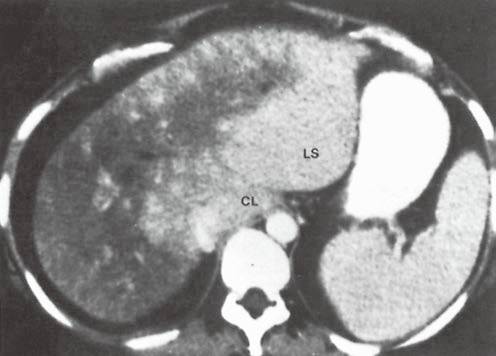

| 淀粉样变性(图7) | 整个肝脏密度弥漫性减低。 | 增大的肝脏内散在的低密度区。 |

图7淀粉样变性